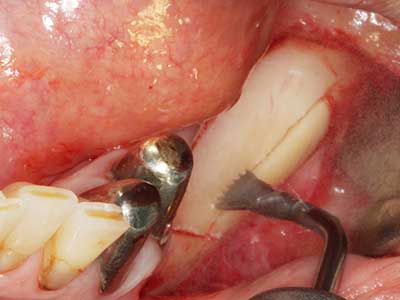

Abb. 17a: CT-Aufnahme eines wachstumsprogredienten Osteoms in unmittelbarer ...

Abb. 17b: Lagebeziehung zum Alveolarkanal mit Nervirritation (laterale und koronare Ansicht).

Abb. 18: Präparation eines Kortikalis-Deckels mit der Piezo-Knochensäge (Piezomed, W&H).

Abb. 19: Operationssitus nach Neurolyse und Osteomentfernung.

Abb. 20: Der entnommene Knochendeckel wird readaptiert und durch eine Osteosyntheseschraube (KLS Martin, Tuttlingen) fixiert.